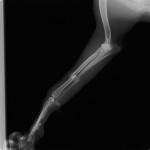

橈尺骨折 ポインター 体重20Kg

手術前

手術後

プレート・スクリューによる整復を行いました。